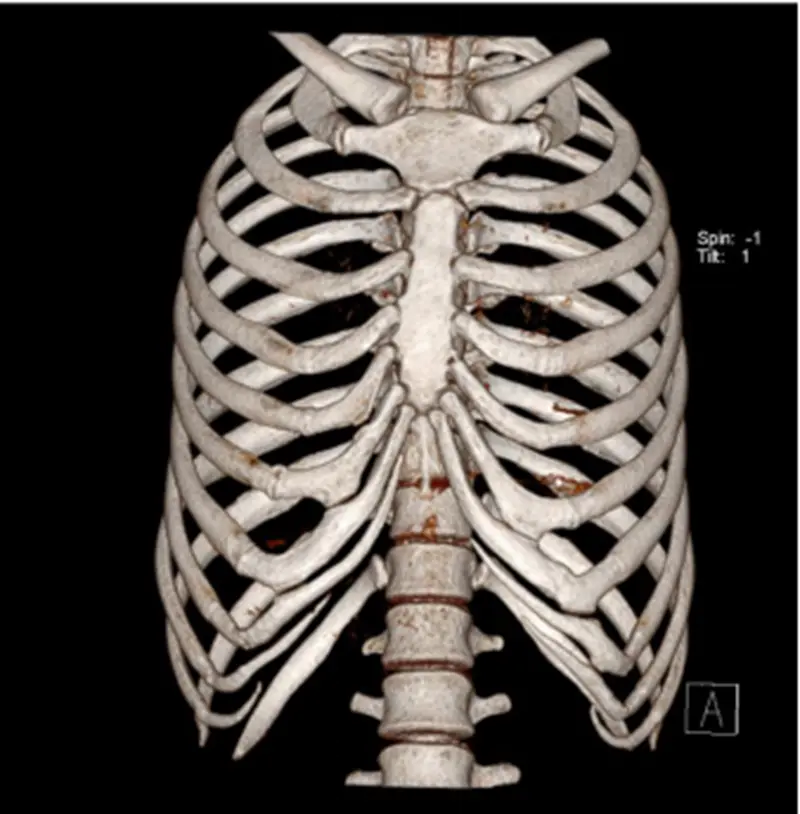

诊断骨关节外伤疾病哪家强 还看ct三维成像检查

诊断骨关节外伤疾病哪家强 还看ct三维成像检查 每日头条

骨关节外伤诊断哪家强 Ct三维成像有优势 北京安通医疗官网

肋骨骨折 你漏诊了吗 螺旋ct三维重建在胸廓骨折中的应用价值